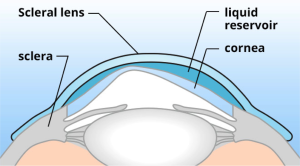

Esta semana quiero comentar este estudio cuyo propósito fué investigar las tasas de éxito y fracaso de la adaptación de la lente escleral en el queratocono grave. Para ello se diseño un estudio de series de casos retrospectivos.

Se propuso la adaptación de lentes esclerales para los 75 ojos incluidos en el estudio. Ocho ojos se sometieron a una cirugía de trasplante debido a la agudeza visual insuficiente con las lentes, intolerancia a los lentes y problemas con el manejo de los lentes. Doce ojos no fueron adaptados debido a la buena agudeza visual en el otro ojo o una contraindicación para el uso de lentes. Tres ojos se adaptaron con éxito con lentes corneales o híbridas. Se prescribieron lentes esclerales en 51 de 75 ojos. La ganancia media en la agudeza visual (lente versus agudeza visual corregida con gafas) fue de 0.54 ± 0.18 (fracción decimal, optotipo Snellen). Siete ojos se perdieron durante el seguimiento, cuatro ojos abandonaron el uso de la lente escleral debido a la incapacidad para manejar las lentes, y cuarenta ojos usaron las lentes en su última visita de seguimiento, con un intervalo de seguimiento promedio de 30.15 ± 12.83 meses.

En conclusión, cuarenta de los 51 ojos con queratocono grave que de otra forma se habrían sometido a cirugía de trasplante se trataron con éxito con el uso de lentes esclerales a largo plazo. De esta manera, la indicación de queratoplastia se redujo a menos de la mitad en esta población de queratocono. Hoy en día, y siempre que no haya una evolución del Queratocono, la lente escleral es una excelente opción de tratamiento.